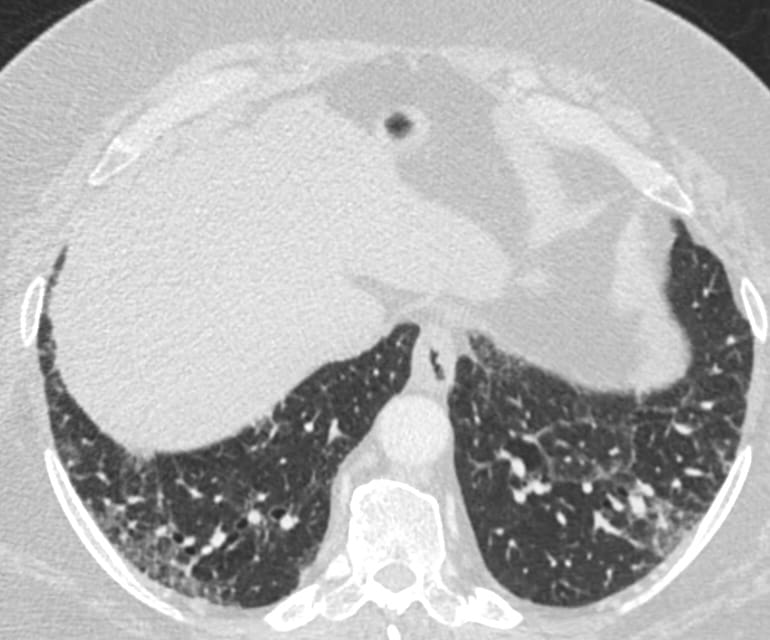

- Usual Interstitial Pneumonia